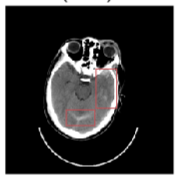

Inverse Problems in Radiology